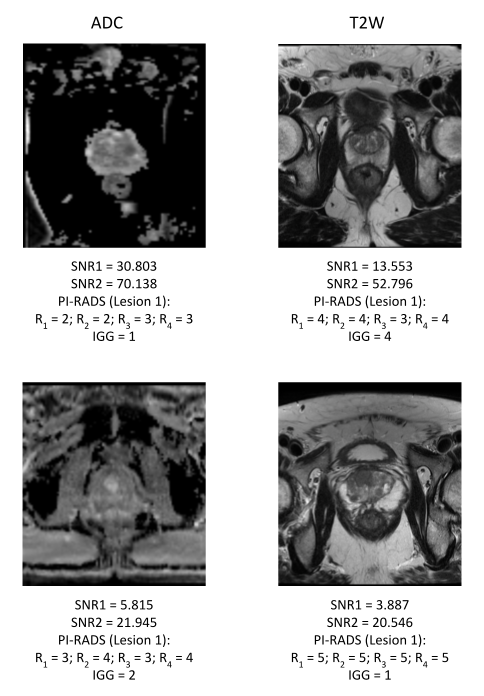

Prostate Imaging Reporting and Data System (PI-RADS) guidelines have been established to standardize radiologists' interpretation of prostate cancer (PCa) on multi-parametric MRI (mpMRI)1. PI-RADS scores (range 1-5) reflect the probability of PCa lesions being clinically significant (csPCa) defined as International Society of Urologic Pathology Grade Group (IGG) > 1 on biopsy1,2. PI-RADS is influenced by several factors including variable image quality (Figure 1) limiting its usage for confirmatory non-invasive PCa diagnosis3,4,5. More recently, biparametric MRI (bpMRI) including T2-Weighted (T2W) and Apparent Diffusion Coefficient (ADC) maps derived from Diffusion Weighted MRI (DWI) are being widely explored for PCa diagnosis8. Recent studies have outlined the need to provide radiologists with high quality MRI for accurate, non-invasive diagnosis of PCa and consequently identified the need to standardize assessment of prostate MRI quality6. While PI-RADSv2 introduced minimum technical standards to reduce image quality variance, they were found to be inadequate3. Recently, PI-QUAL guidelines have been proposed to assess diagnostic quality of prostate MRI. However, they are subjective and can still be influenced by reader interpretation7. Quantitative metrics derived from computational image processing can provide an objective means of assessing MRI quality. In this study, we aim to use the open-source tool MRQy to derive quantitative image quality metrics of prostate bpMRI and evaluate their association with (a) accuracy of PI-RADS in detecting csPCa and (b) inter-reader agreement between PI-RADS scores, on a dataset of n=99 patient studies evaluated by n=4 experienced radiologists.

Figure 1. Bi-parametric MRI sequences of differing quality with corresponding PI-RADS v2.1 scores assigned by readers R1-R4